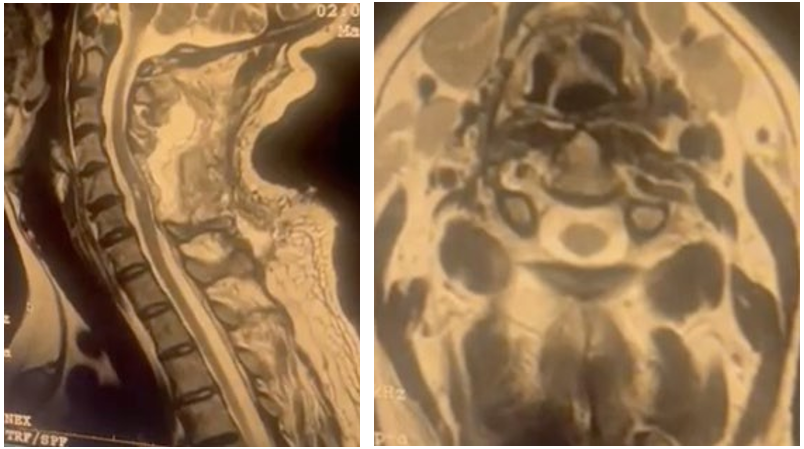

A 43-year-old patient with no significant medical history was admitted with cervical pain of 8 months duration, recently complicated by left cervical neuralgia in the C6 dermatome with paresthesia and numbness in the same area, but without sphincter disorders nor weight loss or fever. Physical examination revealed no neurological deficit and shoulder examination revealed no abnormalities. Spinal MR imaging showed an intramedullary lesion widening the cervical spinal cord at C5-C6, with a popcorn sign and heterogeneous signal on T1- and T2-weighted images, surrounded by a hypointense ring in all sequences (Figure 1), especially in gradient echo, which represents hemosiderin. Susceptibility-weighted imaging shows hypointense lesions, without adjacent intramedullary hemorrhage and contrast enhancement. The diagnosis of cervical medullary cavernoma was confirmed and the patient underwent surgery via a posterior approach to the cervical spine with complete removal of the cavernoma (Figure 2). Postoperative follow-up was easy, except for transient quadriparesis, which disappeared within a few days with physical rehabilitation. The follow-up MRI was satisfactory (Figure 3)

Figure 1: Pre-operative Cervical Spinal MRI showing the C5-C6 Cavernoma